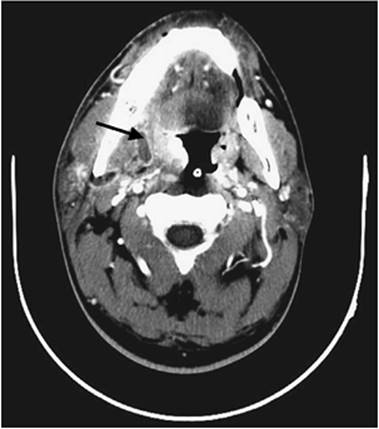

Parapharyngeal Space Abscess

Figure 109.10. Computed tomography (CT) of the neck demonstrating a parapharyngeal space abscess.